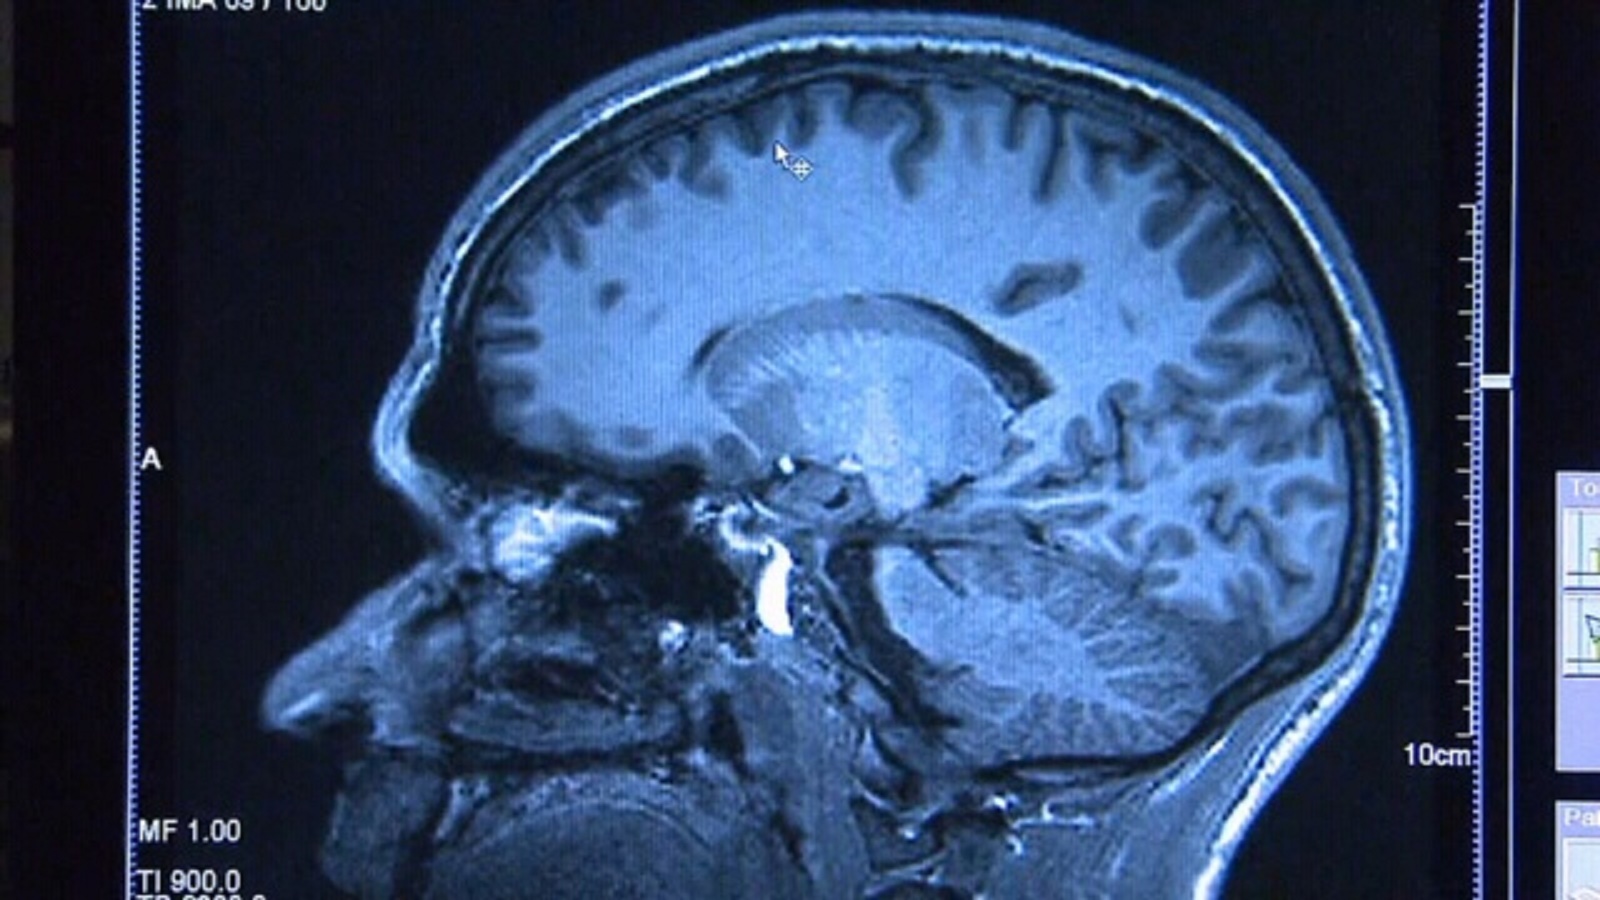

Your brain is hardening your arteries, but not on purpose!